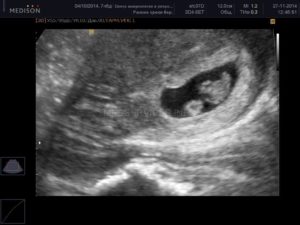

- по результатам ультразвукового исследования в первом триместре (узи при беременности двойней – самый точный показатель).

- УЗИ на 12 неделе беременности;

Считается, что точно увидеть несколько эмбрионов, можно только при помощи УЗИ. На каком сроке определяют многоплодную беременность? Специалист может увидеть данный факт в 5-6 недель. Но, как правило, ее диагностируют во время первого скрининга в 12 недель.

А что же со вторым? Его вовсе не было, потому что в медицине бывают и такие случаи, которые называют «скрытый близнец». При УЗИ на ранних сроках все отображено не совсем четко, поэтому такие ситуации часто встречаются.

- Чтобы исключить малейшую ошибку, при подозрении на беременность близнецами врачи отправляют пациенток на ультразвуковое исследование. Это наиболее точный и достоверный метод обследования. С его помощью врачи получают данные о размерах плода, возможных патологиях. Также УЗИ позволяет получить достоверную информацию, что касается однояйцевой или разнояйцевой беременности.